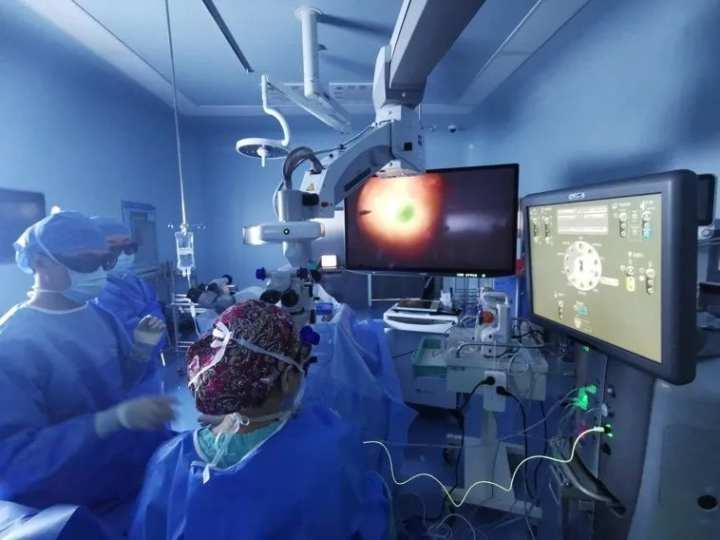

三、种植牙的手术过程

1. 麻醉:首先,医生会为你进行局部麻醉,确保你在手术过程中不会感到疼痛。

2. 切开牙龈:医生会在牙槽骨上切开一个小口,以便植入人工牙根。

3. 植入人工牙根:将人工牙根植入牙槽骨中,这个过程需要一定的技术,医生会小心翼翼地进行。

4. 缝合:完成人工牙根植入后,医生会缝合切口,并为你戴上临时牙冠。